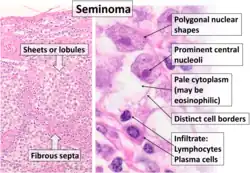

| Histopathology of classical seminoma, with typical features.[1] | |

Microscopic examination shows that seminomas are usually composed of either a sheet-like or lobular pattern of cells with a fibrous stromal network. The fibrous septa almost always contain focal lymphocyte inclusions, and granulomas are sometimes seen. The tumour cells themselves typically have abundant clear to pale pink cytoplasm containing abundant glycogen, which is demonstrable with a periodic acid-Schiff (PAS) stain. The nuclei are prominent and usually contain one or two large nucleoli, and have prominent nuclear membranes. Foci of syncytiotrophoblastic cells may be present in varied amounts. The adjacent testicular tissue commonly shows intratubular germ cell neoplasia, and may also show variable spermatocytic maturation arrest.[5]